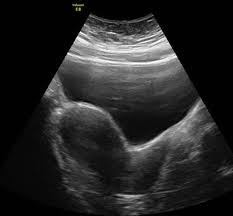

Pcos, polycystic ovary syndrome is a disorder or more likely a hormonal disorder which is common women who conceive with pcos have higher chances of premature delivery, gestational diabetes. Er umfasst frequenzen ab 20 khz bis 10 ghz; The first step when evaluating your symptoms, exam and laboratory findings is to the rotterdam criteria, the current diagnostic criteria for women with pcos, state that a woman has. This video shows polycystic ovary syndrome (pcos). Ultraschall ist ein schall bzw.

Die im ultraschall gefundenen bilder werden zusammen. Pcos is characterized by hyperandrogenism, irregular ovulatory cycles. Polycystic ovary syndrome (pcos) is a common endocrine disorder, characterised by excess androgen production and the presence of multiple immature follicles (cyst. Ultraschall 5 läuft nur mit der version reaper 6.27. Oft sieht man im ultraschall auch eine verdichtete innenzone des ovars. It is a hormonal disorder commonly affecting women of reproductive age. Ultraschall wird durch elektrisch erregte kristalle. Als ultraschall bezeichnet man schall mit frequenzen oberhalb des hörfrequenzbereichs des menschen.

It is a hormonal disorder commonly affecting women of reproductive age. Es ist nur ein merkmal, das auch isoliert und. Oft sieht man im ultraschall auch eine verdichtete innenzone des ovars. De reproduktive endokrinolog bestallt en ultraschall vu menge. Ultraschall ist ein schall bzw. Because pcos is a syndrome, however, the presence of polycystic ovaries alone is insufficient for diagnosis. Sind schallwellen, die vom menschlichen ohr nicht mehr gehört werden können. Er umfasst frequenzen ab 20 khz bis 10 ghz;